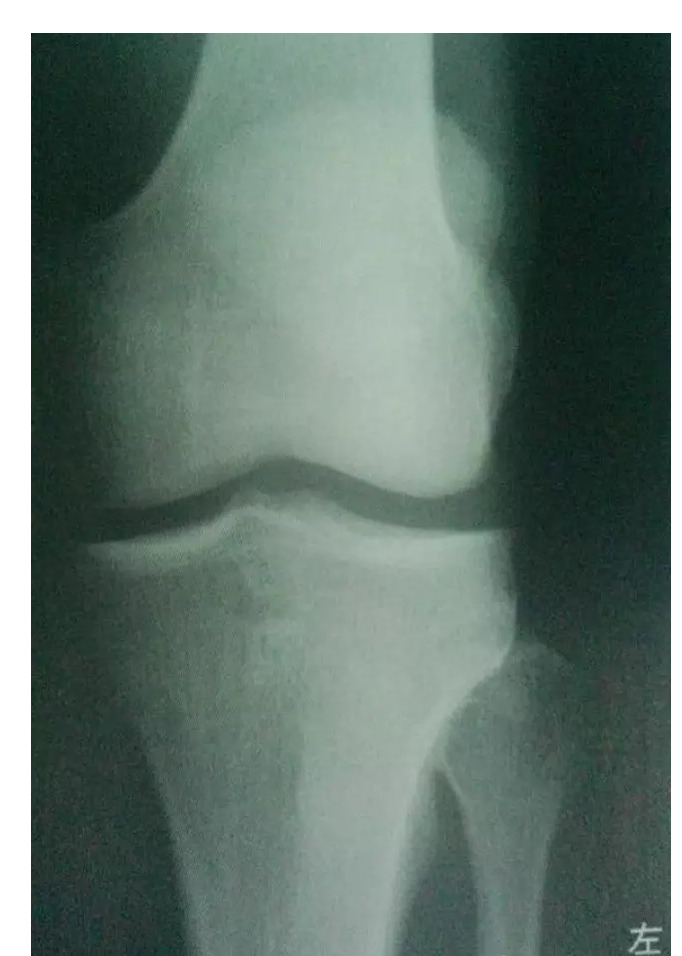

本病的X线表现主要以不同程度的关节间隙狭窄及关节内骨赘形成为特点,程度不同可有不同的分级。

膝骨性关节炎X线片